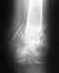

Похоже, есть смысл не ждать, а переделать.

Прошло больше месяца. Есть смысл еще раз посмотреть на пациента и свежий снимок.